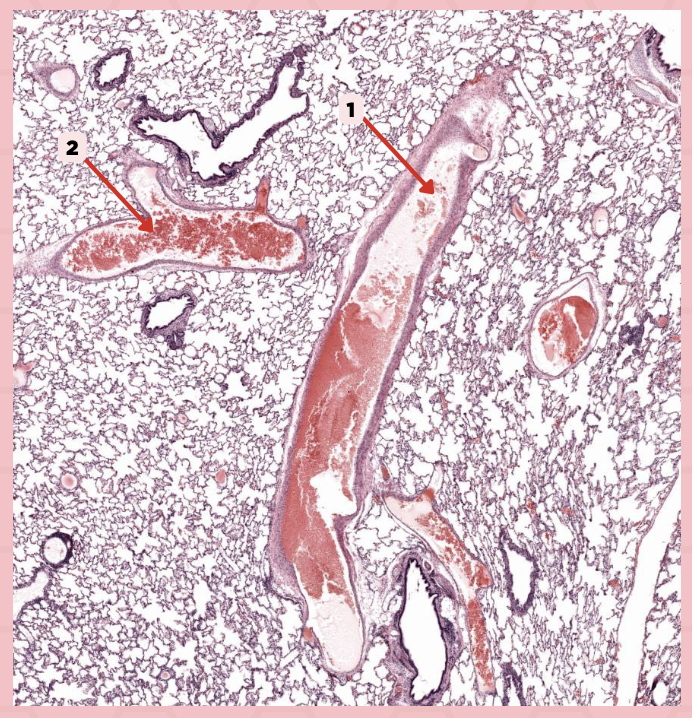

Deoxygenated blood

What type of blood does vessel No. 1 carry?

Connective tissue septae

Where would No. 2 be located?

Pulmonary artery

Identify the structure labeled as 1.

Tributary of pulmonary vein

Identify the structure labeled as 2.

Oxygenated blood

What type of blood does this vessel supply?

Bronchial artery

Identify the structure labeled as 1.